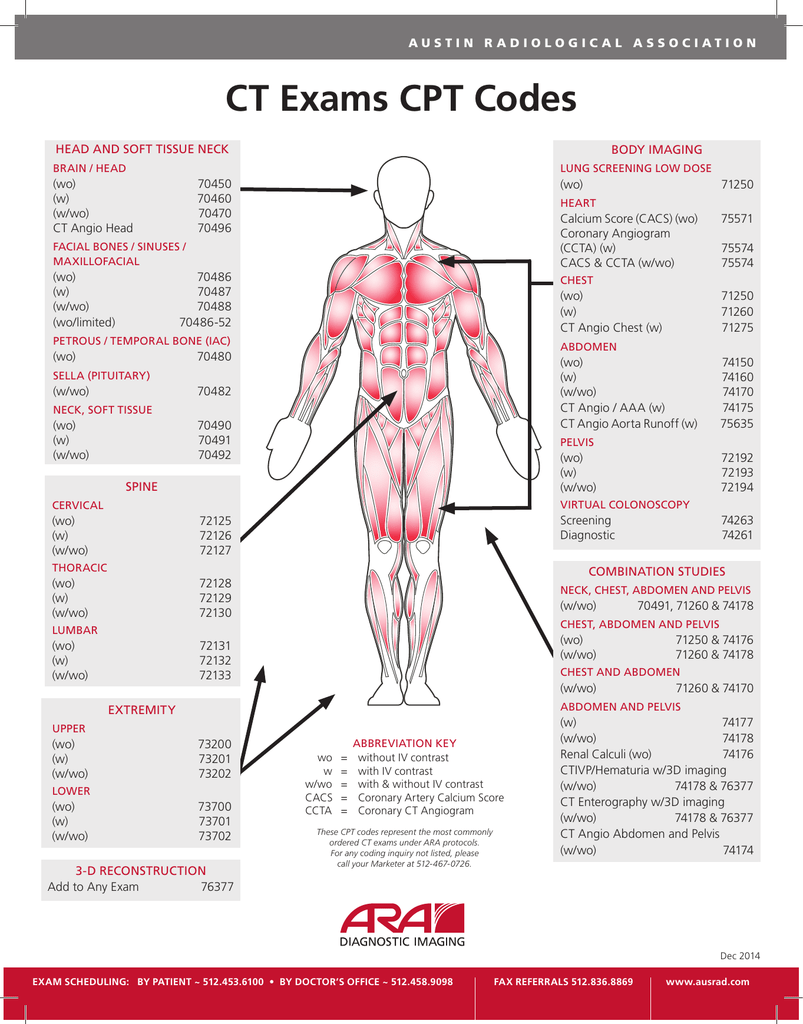

2025 Cpt Codes List Rosie C Pearce

https://s2.studylib.net/store/data/018238018_1-bd043e89c3168d7c0fc27085c3a82070.png

Mri Knee Cpt Code 2024 Alyson Andreana